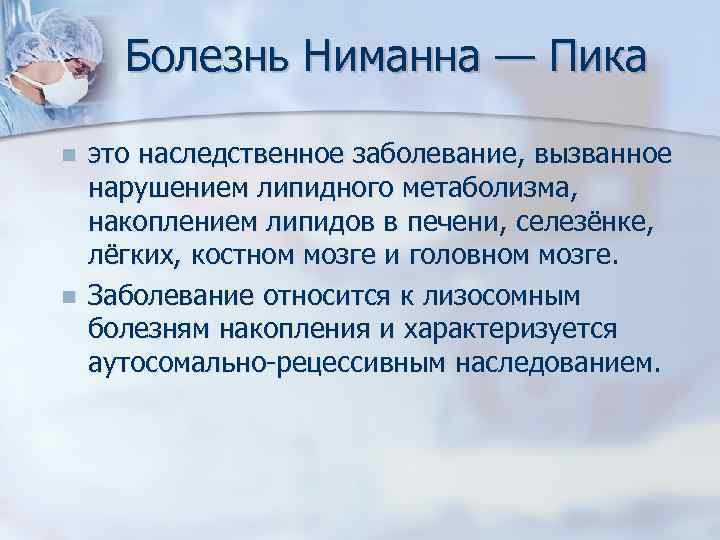

Болезнь Нимана-Пика Тип А: Симптомы и лечение